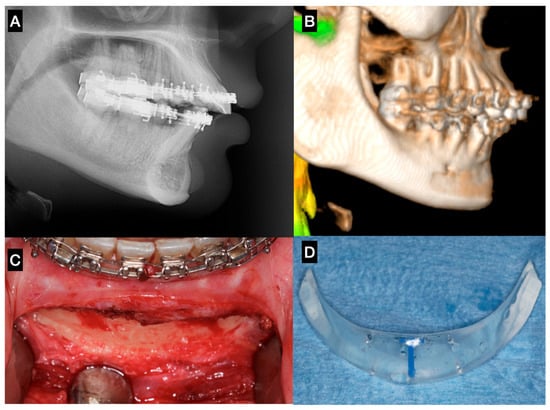

4.2. Implant Materials

A variety of materials have been described for use in facial augmentation and reconstruction procedures associated with orthognathic surgery, particularly in the midface and lower facial thirds [6,12,19]. Fattahi et al. (2017) [23] described the use of silicone implants for infraorbital rim augmentation to correct deficiencies around the infraorbital foramen. Silicone remains popular due to its availability in preformed shapes, ease of placement, and lack of fixation requirements (in some cases). However, its limitations include poor integration, fibrous capsule formation, underlying bone resorption, and a potential for displacement or extrusion over time (Figure 3).

Figure 3. Sagittal chin augmentation using a standard silicone implant in a patient presenting with a Class II skeletal deformity. The patient sought evaluation due to implant mobility detected clinically four years after placement. (A) Lateral cephalometric radiograph showing pronounced bone resorption beneath the implant, with proximity to the apices of the mandibular incisors. (B) 3D reconstruction confirming a well-defined resorption defect extending toward the mental foramen. (C) Post-explantation intraoperative image demonstrating the full extent and depth of the osseous defect. (D) Removed standard silicone implant, evidencing its non-anatomic contour and excessive posterior extension, factors that likely contributed to instability and bone resorption—Image from the authors’ personal archive.